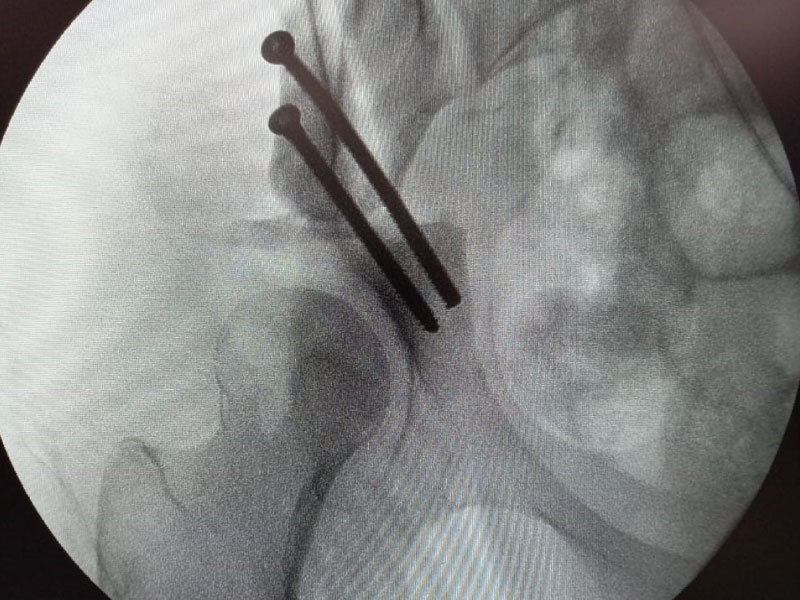

Caso No. 10 - Luxofractura de tobillo

Preoperación

Rx de perfil transoperatoria

Rx transoperatoria anteroposterior

Tratamiento: Cirugía: reducción abierta y fijación interna